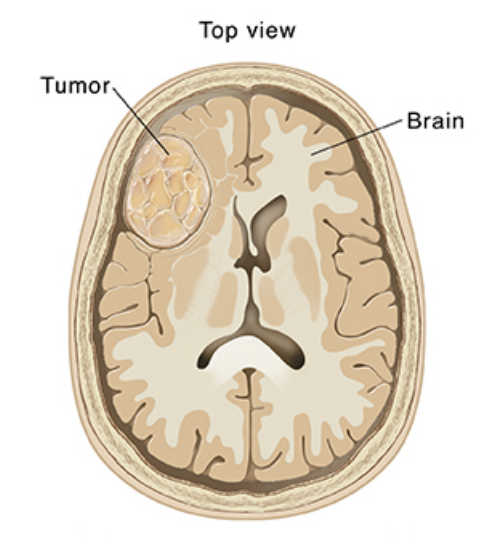

Brain Tumors

What are Brain Tumors? (click here)

Who will you meet and common terms? (click here)

Surgery for Brain Tumors (click here)

Biopsy for Brain Tumors (click here)